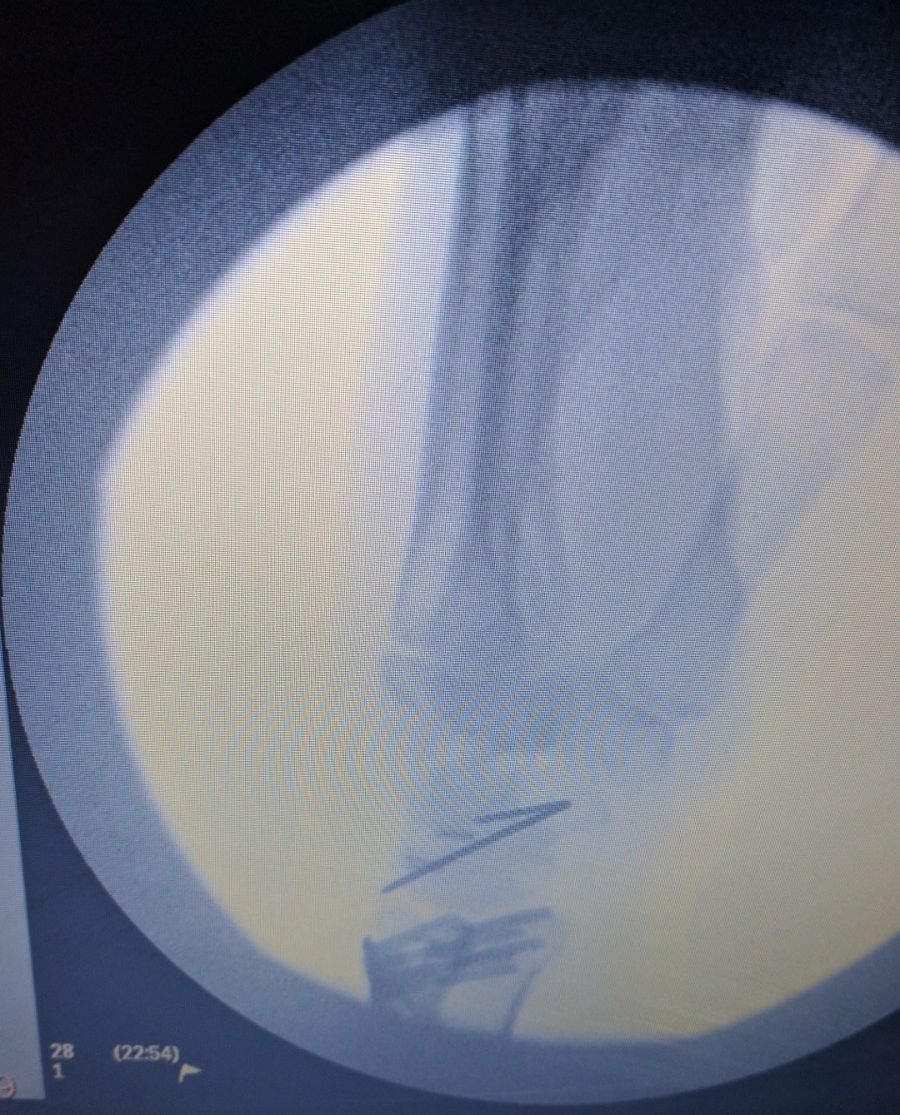

The plate in position.

Here with the wire removed.

Surgery complete.